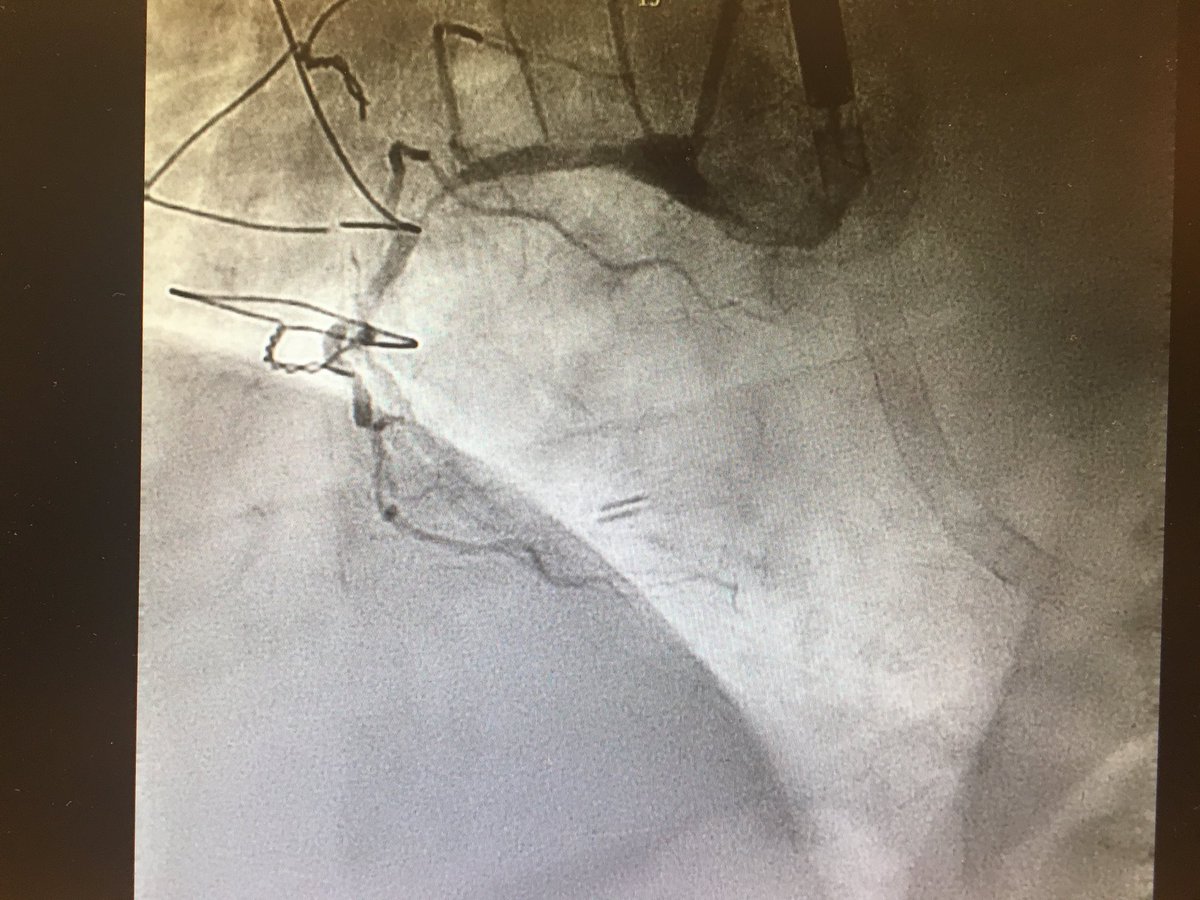

#CHIPcase 74yo male, LM+3vd, LVEF 17%, previous non-functionant CABG. Previous inferior MI without inferior viability. Actual NSTEMI with cardiogenic shock. Sent to our centre for Complex PCI @foroic @belcid7 @sbrugaletta @mmamas1973 @shci_sec @jedicath @hect2701 @Xavi_Carrillo7